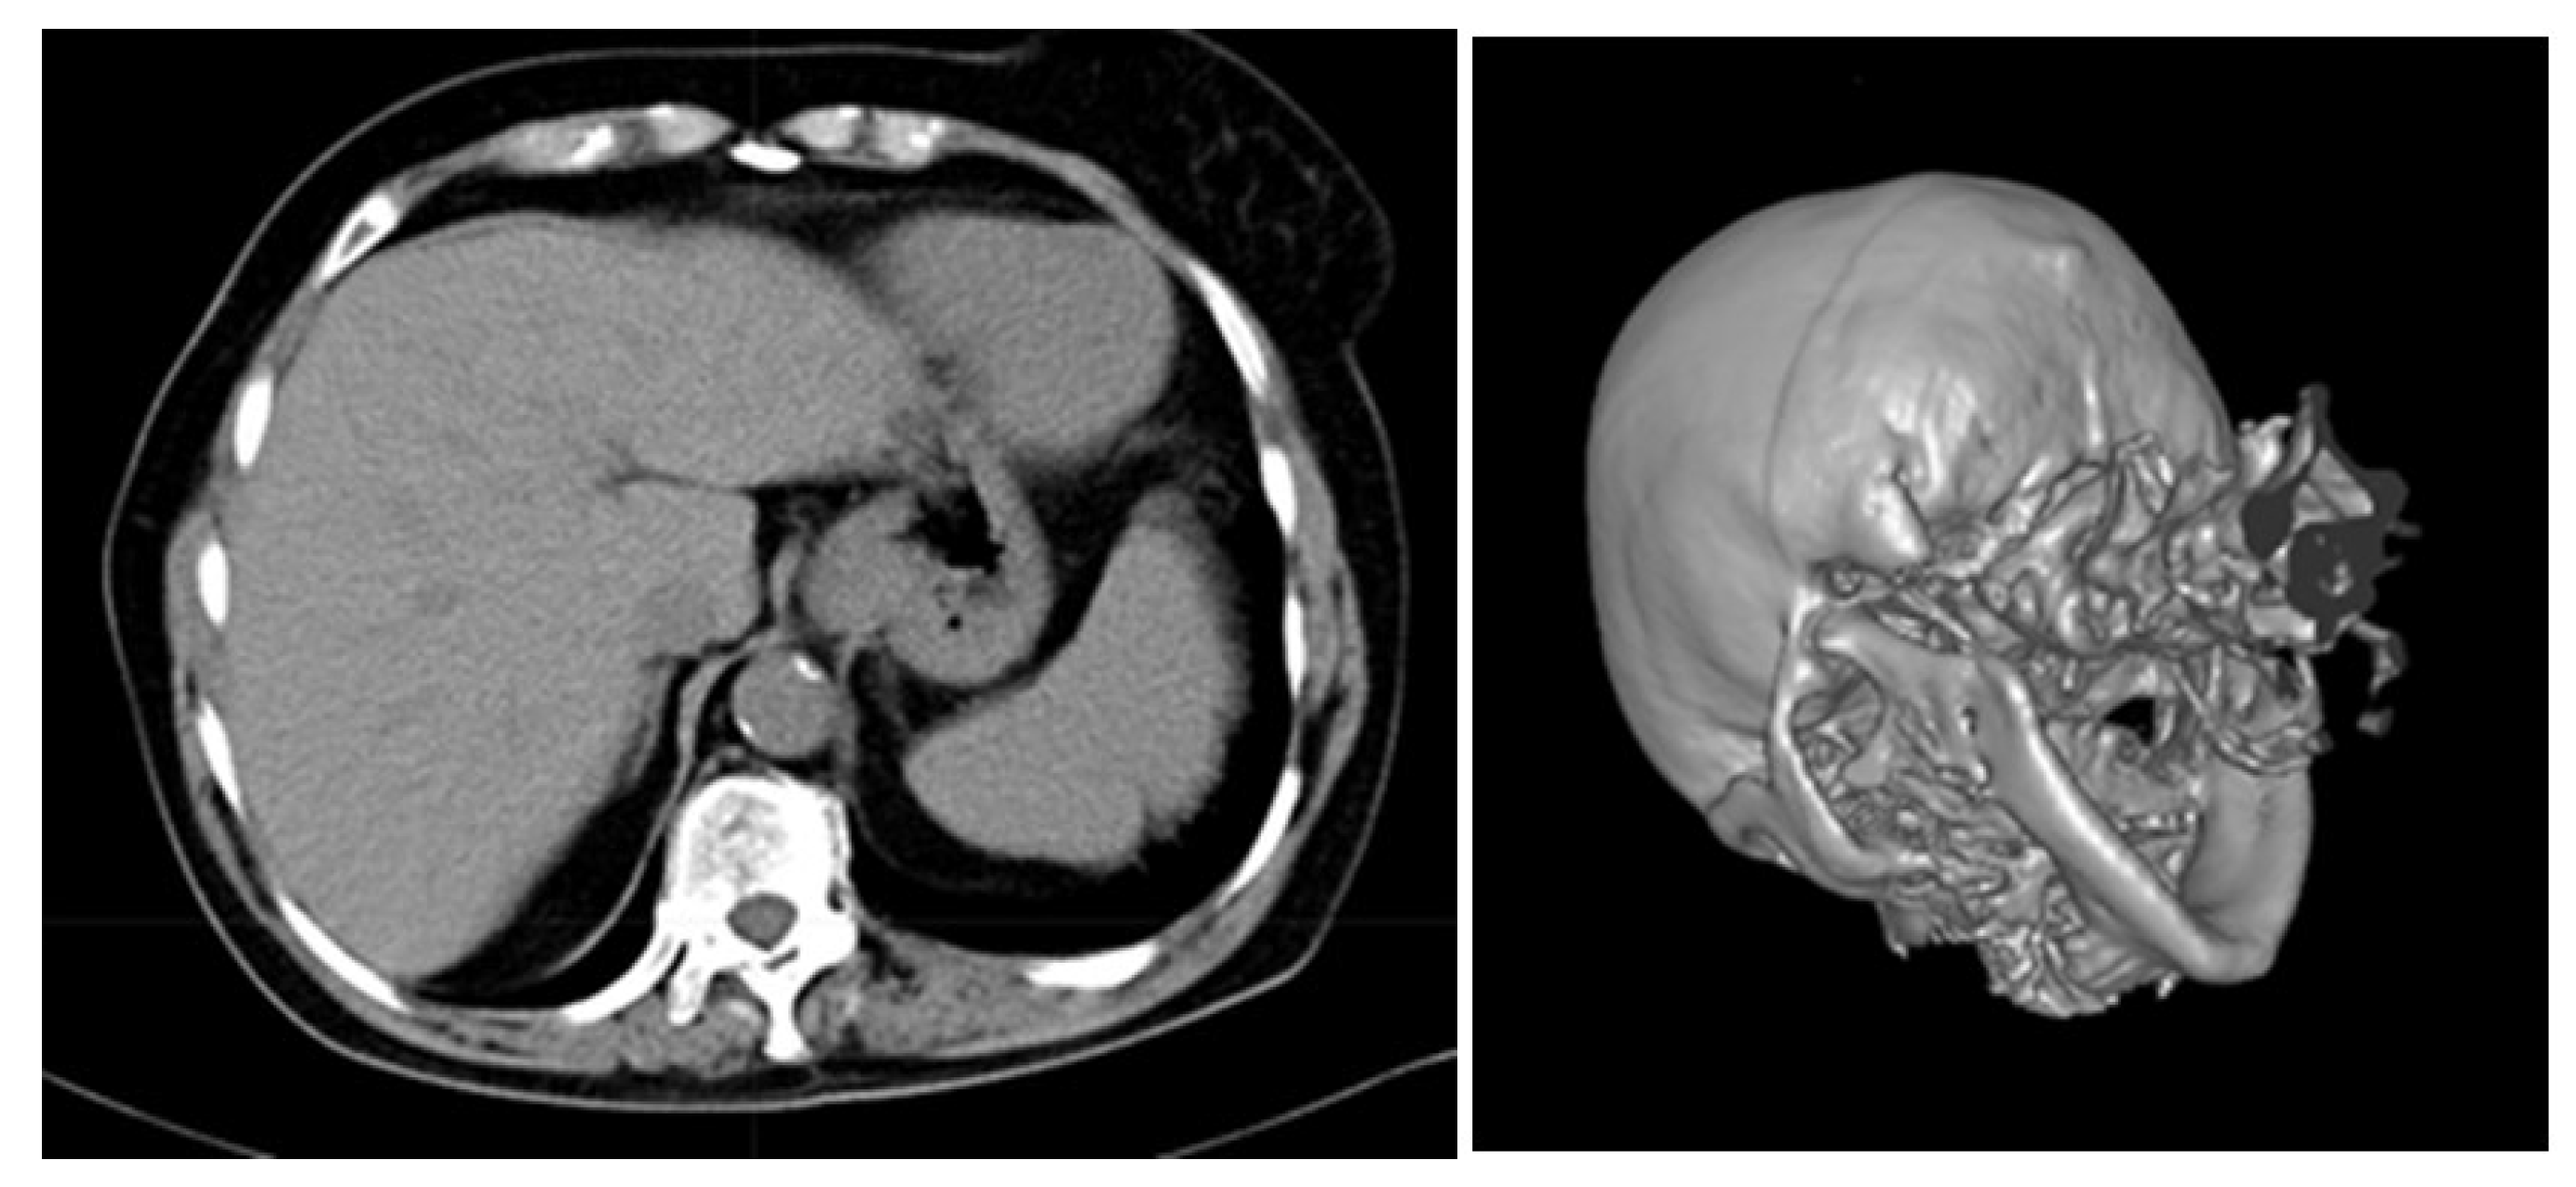

Many techniques including deep and machine learning [44] have been developed for the segmentation [45], reconstruction [46], and registration [47] of images, including medical ones. VanityX supports various volume rendering techniques such as texture-based rendering, ray-cast rendering, and rendering using transfer functions. With reference to Figure 15, we render a slice of a human abdomen (liver) and a human skull. The slice of a human abdomen is anonymized and rendered using texture-based rendering, where each axial slice is represented as a texture mapped (sampled) onto a quad. The human skull is rendered using transfer functions that map scalar data onto color and opacity to depict relevant features of the model being rendered.

Figure 15. Volume rendering via textures and transfer functions. On the left is a model provided courtesy of Dragan Schwarz from hospital Radiochirurgia, Croatia, while the second model is a free one.